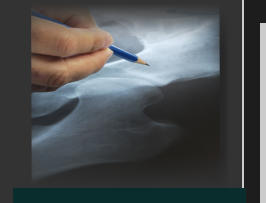

Bio Total hip, is a innovative device with the potential of repairing and replacing joints by accessing joints through the femur neck. This will minimise the need to perform Arthroplasty or Total Hip Prosthesis which then reshape and resurface the bone between joints. The Bio Total Hip performs arthroscopy without damaging articular capsules by introducing biological materials between joints. This less-invasive surgical treatment will revolutionize major hip and major joint surgery due to its minimalistic approach. This will be beneficial to patients suffering early stages of osteoarthrosis within damaged joints. Bio-Total Hip incorporates ridges on the outer member surface which grasp the femur neck. The inner member is telescopic and interlocks with the outer member via the ridges on its external surface. At its joint end there is a mini head made from biological materials which sit neatly within the joint and which will then fill out the space between the joints. This Mini head piece can be detached and replaced by an umbrella type tool which expands and covers the head of the femur thus mechanically resurfacing any imperfections. This will allow the joint to function as it used to. Via Xray, a small tunnel is then drilled and directed towards the fovea of the ligamentum capitis or around the ligament of the femur head. This creates a depression area in the insertion point of the ligament. This ligament will be moved in order to visualise the entire hip joint as it rotated, flexed and extended. Could this abnormal wear an tear of joint surfaces be what initiates the original lesion in the articular cartilage, which eventually destroys the joint. The fevoea of the ligament is a depression that does not come into contact with the Acetabulum wall, therefore after arthroscopy it is easier to cover with bone pegs, then resurface the area with bio materials. Arthroscopic devices inserted into the tunnel facilitate a visual inspection of the joint and localize damaged areas withiin the articular cartilage. The use of stem cells from cultivated cartilage will allow the joint to be ‘fixed’ with minimal effort. In similar trans-cervical tunnels and in late osteoarthritis, its possible to insert bio materials to fill the joint space. Bio Total Hip has the technological advantage in comparison to current surgical procedures as it removes only the neck and head of damaged joints throughout stages of articular cartilage damage by reshaping and resurfacing damaged surfaces, thus keeping the capsule and blood supply intact. Utilising a visual device to resurface the joint, the need for total hip, or joint replacement surgery will be reduced dramatically. This micro surgical procedure creates a new layer/surface to minimise friction to once again enable smooth gliding between the joint surfaces. Flushing joints and removing foreign bodies will allow the repair of any soft structural damage within joints and reshape the area. An inflatable bladder attached to a telescopic member compresses the Bio material, then resurfaces the joint via an adjustable telescopic mechanism with a profiled head .This will sit proud within the joint and create an artificial space allowing free movement of arthritic joints. This makes it possible to repair any osteosynthesis of a fractured femur neck, after the joint turns arthritic. The joint space is accessible when the pre-inserted pin is removed, which allows arthroscopic devices to tunnel further towards any diseased or damaged areas. This is when repair can then be performed via the use of bio-materials. The outer part of the device remains within the socket which is beneficial if access to the joint is needed again. This process allows patients to be mobile soon after surgery, which is not possible with today’s current procedures.

Bio Total hip, is a innovative device with the potential of repairing and replacing joints by accessing joints through the femur neck. This will minimise the need to perform Arthroplasty or Total Hip Prosthesis which then reshape and resurface the bone between joints. The Bio Total Hip performs arthroscopy without damaging articular capsules by introducing biological materials between joints. This less-invasive surgical treatment will revolutionize major hip and major joint surgery due to its minimalistic approach. This will be beneficial to patients suffering early stages of osteoarthrosis within damaged joints. Bio-Total Hip incorporates ridges on the outer member surface which grasp the femur neck. The inner member is telescopic and interlocks with the outer member via the ridges on its external surface. At its joint end there is a mini head made from biological materials which sit neatly within the joint and which will then fill out the space between the joints. This Mini head piece can be detached and replaced by an umbrella type tool which expands and covers the head of the femur thus mechanically resurfacing any imperfections. This will allow the joint to function as it used to. Via Xray, a small tunnel is then drilled and directed towards the fovea of the ligamentum capitis or around the ligament of the femur head. This creates a depression area in the insertion point of the ligament. This ligament will be moved in order to visualise the entire hip joint as it rotated, flexed and extended. Could this abnormal wear an tear of joint surfaces be what initiates the original lesion in the articular cartilage, which eventually destroys the joint. The fevoea of the ligament is a depression that does not come into contact with the Acetabulum wall, therefore after arthroscopy it is easier to cover with bone pegs, then resurface the area with bio materials. Arthroscopic devices inserted into the tunnel facilitate a visual inspection of the joint and localize damaged areas withiin the articular cartilage. The use of stem cells from cultivated cartilage will allow the joint to be ‘fixed’ with minimal effort. In similar trans-cervical tunnels and in late osteoarthritis, its possible to insert bio materials to fill the joint space. Bio Total Hip has the technological advantage in comparison to current surgical procedures as it removes only the neck and head of damaged joints throughout stages of articular cartilage damage by reshaping and resurfacing damaged surfaces, thus keeping the capsule and blood supply intact. Utilising a visual device to resurface the joint,